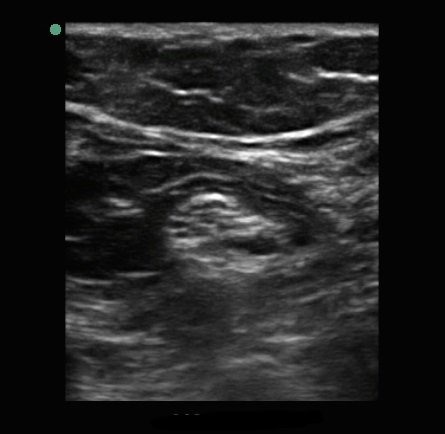

腘神经 1 图像